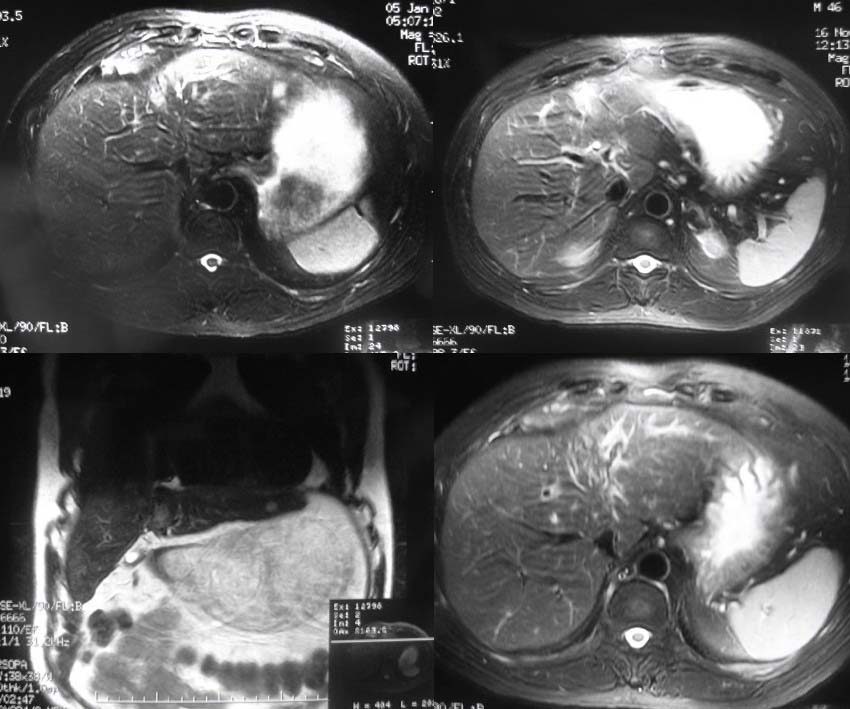

男性46岁,2005年5月份因原发性肝癌在上海中山医院手术,术后2个月即在手术周围新生肿瘤组织,在我院行介入治疗,治疗后5个月后随访在栓塞病灶的周围再次出现新病灶,患者再次奔赴中山医院手术,术后8个月复查afp升高,于我院先后两次介入治疗,06年11月mr复查未见复发病灶,07年复查即发现新病灶(见mr片),本次介入术中欲分别超选肝左和肝右动脉,但超选择左肝动脉失败,缘由是从肝固有动脉发出后突然转向左下方,同时轻度旋转,为确保疗效,故采取不得已的办法:栓塞胃十二指肠动脉.

mr图像: